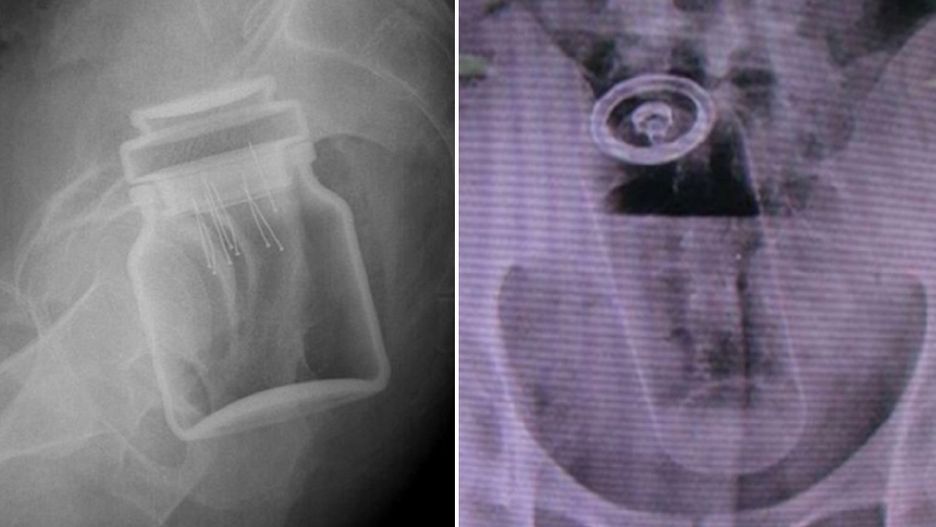

/ 8Słoik z kawą

Obraz

© imgur.com

Podobno pacjent był tak zawstydzony, że nawet nie próbował się tłumaczyć.